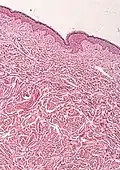

- Histological test